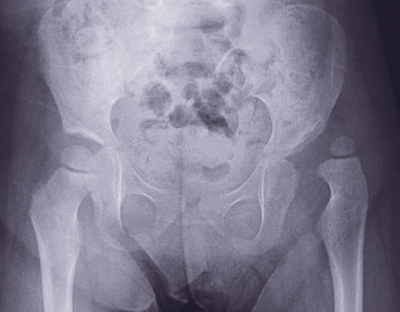

يشكل الخلع الوركي الولادي لدى الأطفال (Developmental dysplasia of the hip) من أهم المشكلات الشائعة لدى الأطفال, فمن المعروف أن مفصل الورك يتكون من عظمتين هما التجويف الحقي والطرف العلوي لعظمة الفخذ المسمى برأس عظمة الفخذ، وفي الوضع الطبيعي تكون هاتان العظمتان متقاربين ببعضهما البعض ويزيد استقرارهما ومحافظتهما على ذلك الوضع الأربطة والعضلات المحيطة بهما، أما في حالة الخلع الولادي يخرج رأس عظمة الفخذ من التجويف الحقي.

ولذا التدخل الجراحي يعتمد على عوامل عدة أهمها: أولاً: مقدار درجة الخلع (إما باستخدام الأشعة السينية أو الأشعة الصوتية)، حيث توجد علامات عدة تبين مقدار الخلع وشدته، ثانيًا: عمر الطفل وقت العملية؛ فالعمر المناسب لإجراء الطفل العملية يكون في السنة الأولى من الإصابة، فإذا زاد عمر الطفل وتأخر في التشخيص تزيد العملية صعوبة وتزيد نسبة فشلها ونسبة مضاعفاتها، حيث لا يفضل عملها بعد عمر الثامنة إذا كان الخلع في كلا الوركين أو عمر العاشرة إذا كان الخلع في جهة واحدة. ولهذا ينصح جميع الأسر الذين لديهم تاريخ عائلي للخلع الولادي بضرورة إجراء الفحص المبكر لأطفالهم مما يسهم في الوصول إلى نتائج مرضية وإيجابية والحد من مضاعفاته عند تأخر التشخيص.